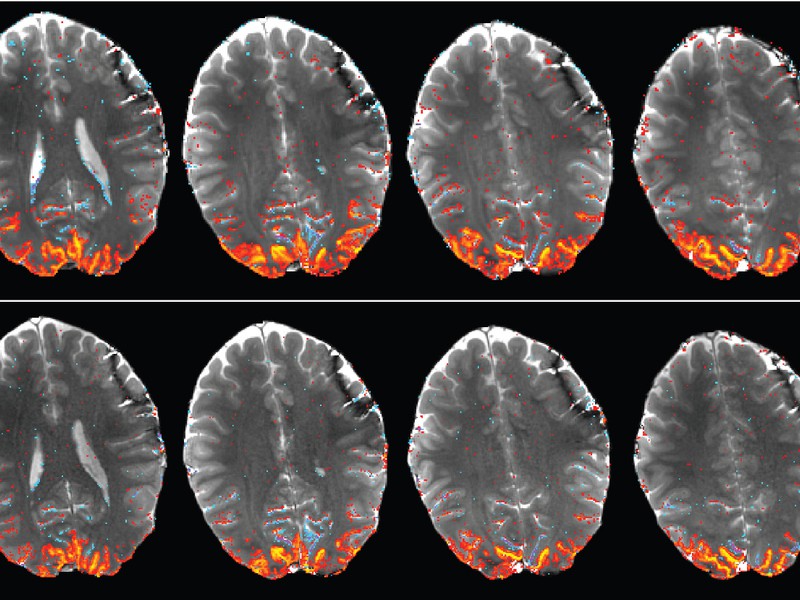

Verschiedene MRT-Schnittebenen durch eine aktivierte Sehrinde: Die bei sehr hohen Magnetfeldern aufgenommenen MRT-Scans sind deutlich detaillierter als herkömmliche Aufnahmen. [weniger]

Im ultrahohen Magnetfeld lässt sich die Gehirnaktivität genauer nachweisen. Je stärker, desto besser? Auf Magnetresonanztomografie-Magneten scheint das zuzutreffen - wenn die richtige Methode eingesetzt wird. Wissenschaftler der Universität Tübingen und des Max-Planck-Instituts für biologische Kybernetik forschen an einer hochauflösenden MRT-Messmethode. Damit gelang es ihnen, Hirnstrukturen um ein Vielfaches genauer darzustellen und Gehirnaktivität besser zu lokalisieren. Verschiedene MRT-Schnittebenen durch eine aktivierte Sehrinde: Die bei sehr hohen Magnetfeldern aufgenommenen MRT-Scans sind deutlich detaillierter als herkömmliche Aufnahmen. In der funktionellen Magnetresonanztomografie (fMRT) hängt die Aussagekraft der Aufnahmen stark von der Signalstärke und damit von der Magnetfeldstärke des Gerätes ab. Eine hohe Auflösung ist für die richtige Interpretation des Signals wichtig, da die Nervenzellaktivität durch MRT nur indirekt gemessen werden kann.